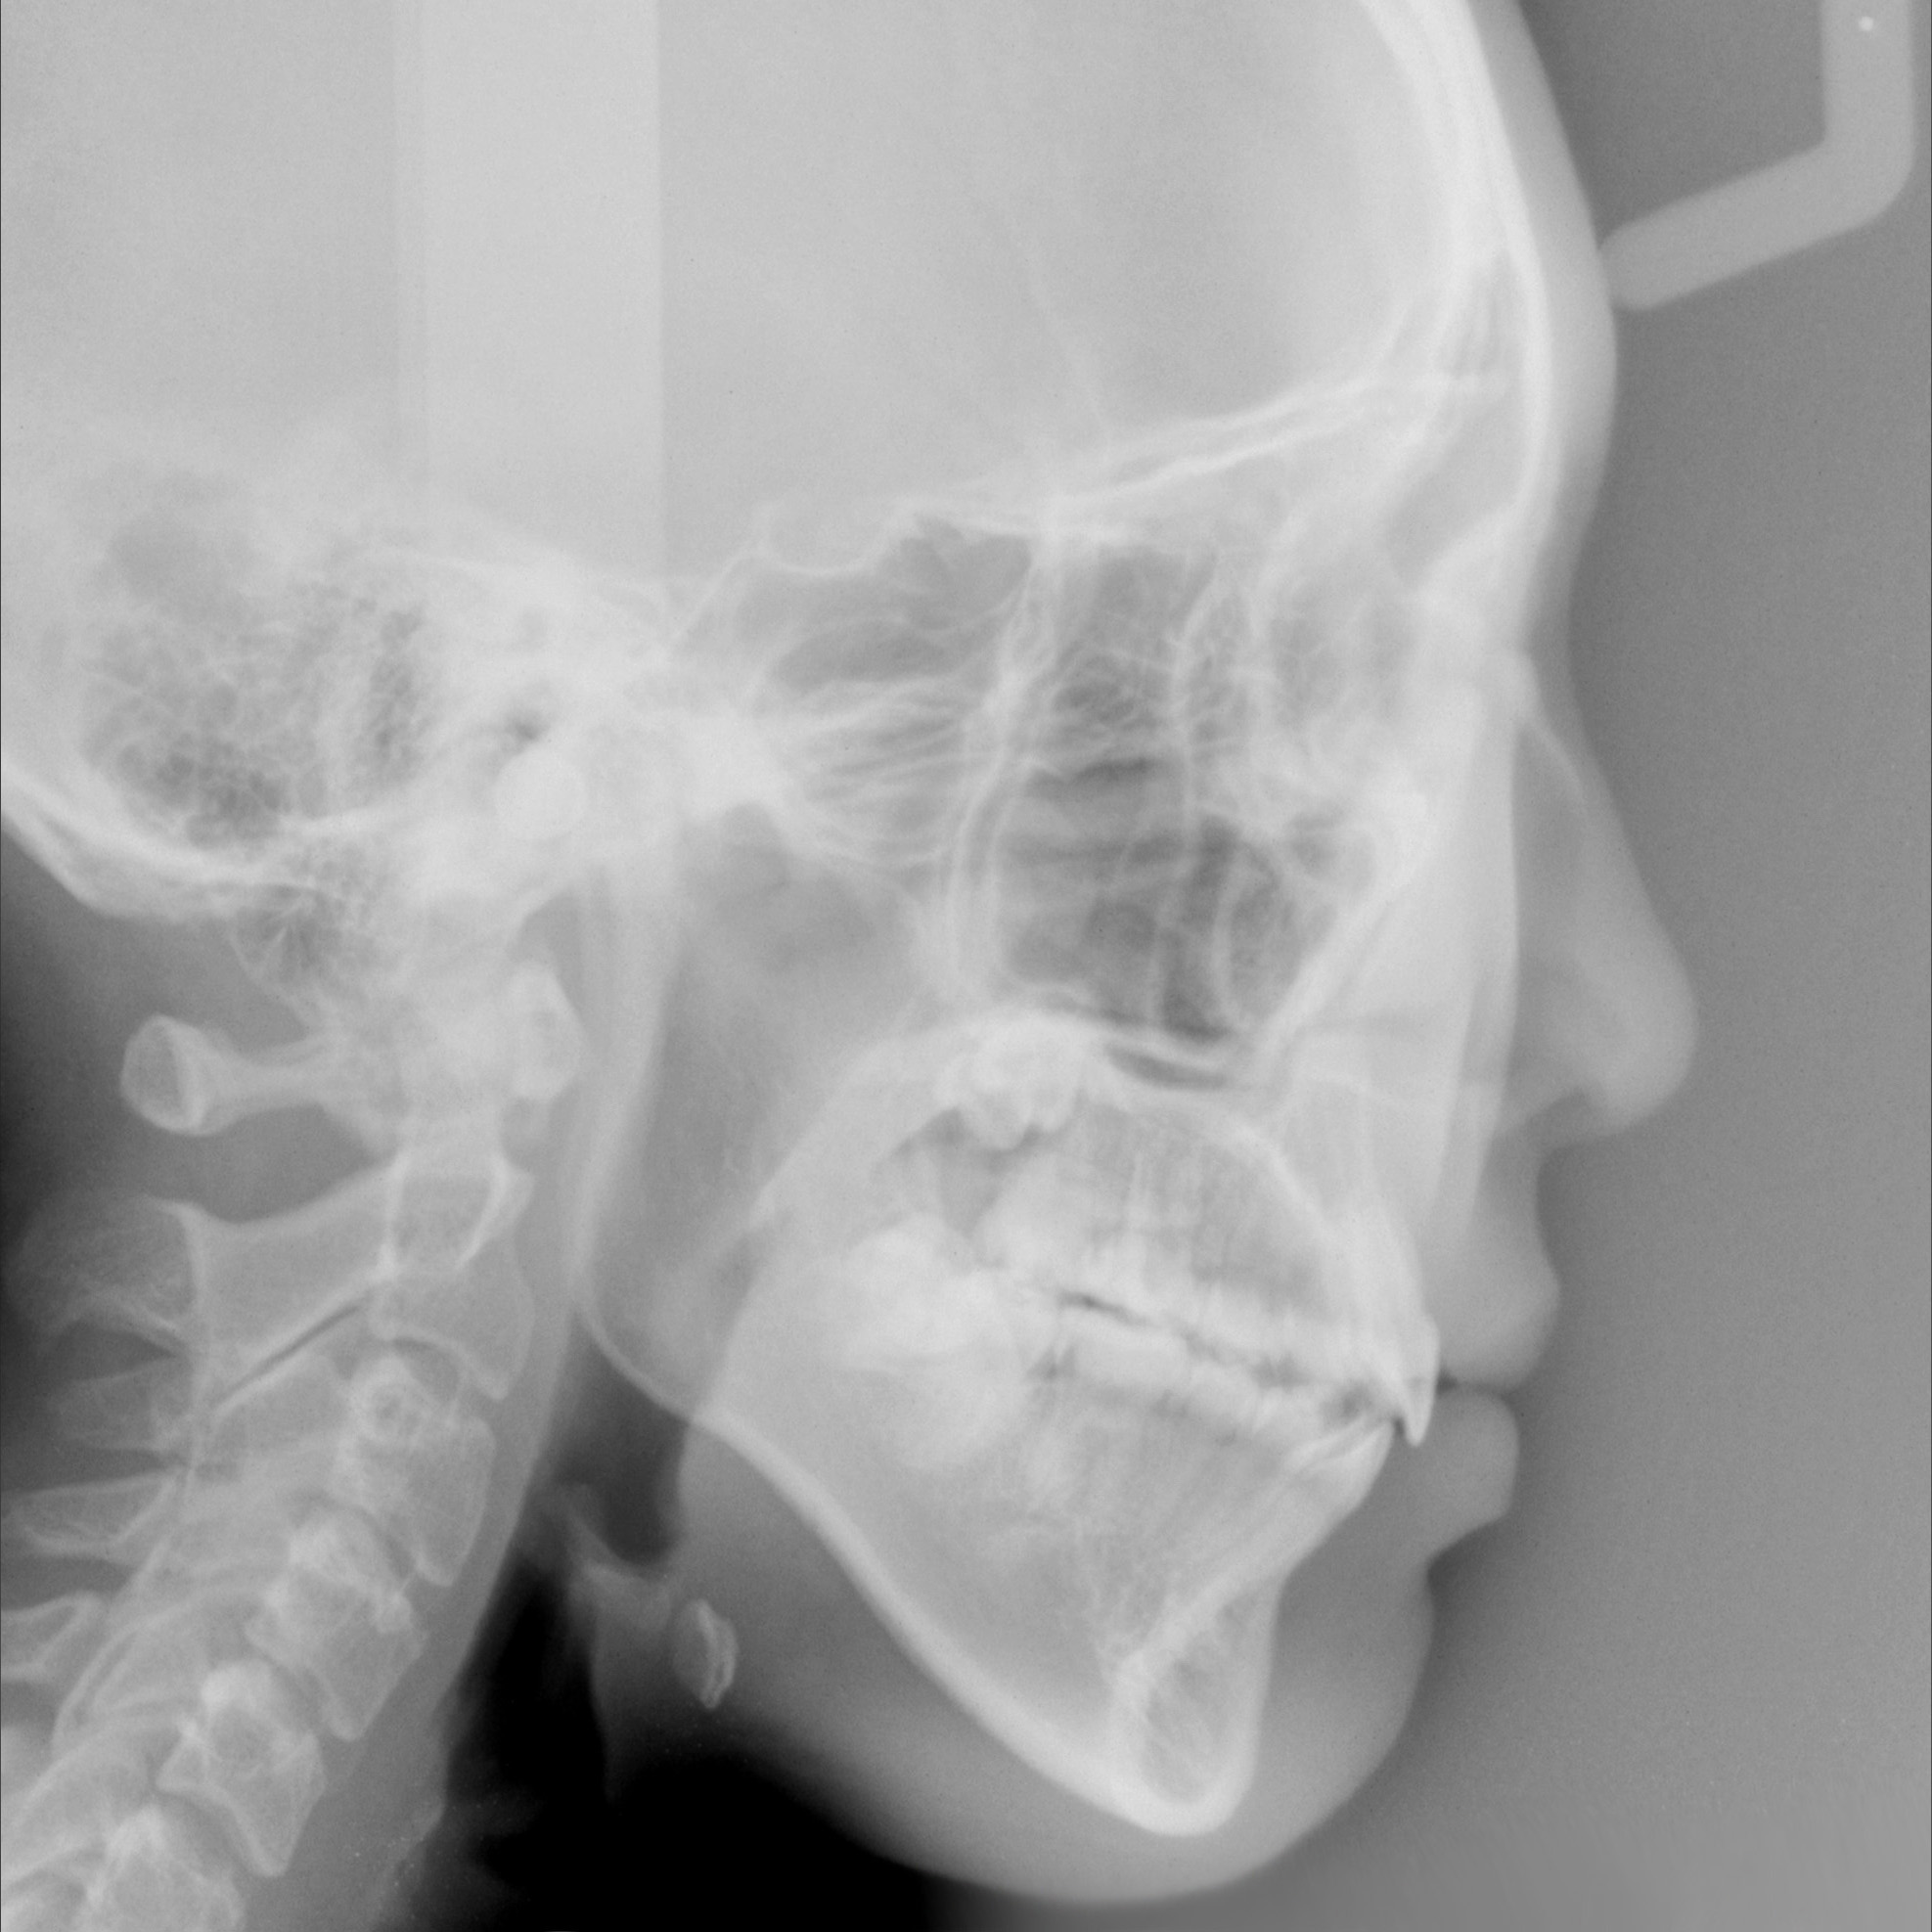

新着情報 526 治療後セファロ側面 Tweet 投稿日 : 2019年10月27日(日)カテゴリー : コメントを残す コメントをキャンセルメールアドレスが公開されることはありません。 * が付いている欄は必須項目ですコメント 名前 * メール * サイト 526 治療後セファロ側面 ≫